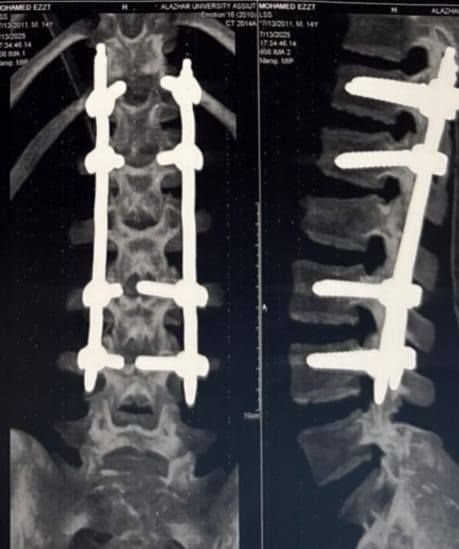

وقال المستشفى في بيان له: وبعد التقييم الإكلينيكي ومناظرة الأشعة، تبين وجود كسر في الفقرة القطنية الثانية، دون وجود علامات لإصابة عصبية مصاحبة، وبعد مناقشة الحالة ضمن الفريق الطبي المتخصص، تقرر التدخل الجراحي لتثبيت الفقرات القطنية والصدرية باستخدام تقنية التثبيت عن طريق الجلد (Percutaneous Fixation)، وهي من التقنيات الحديثة التي تهدف إلى:

وتابعت: أُجريت العملية تحت تأثير التخدير الكلي، دون حدوث مضاعفات أثناء أو بعد الجراحة، وتم نقل المريض إلى غرفة الإفاقة بحالة عامة مستقرة، ويُتابَع حاليًا في القسم المختص، مضيفة: يُنفذ هذا النوع من التدخلات الجراحية بوحدة العمود الفقري بقسم جراحة المخ والأعصاب، على يد فريق طبي متخصص وفي بيئة طبية مزودة بالأجهزة اللازمة للتوجيه والتصوير أثناء الجراحة.